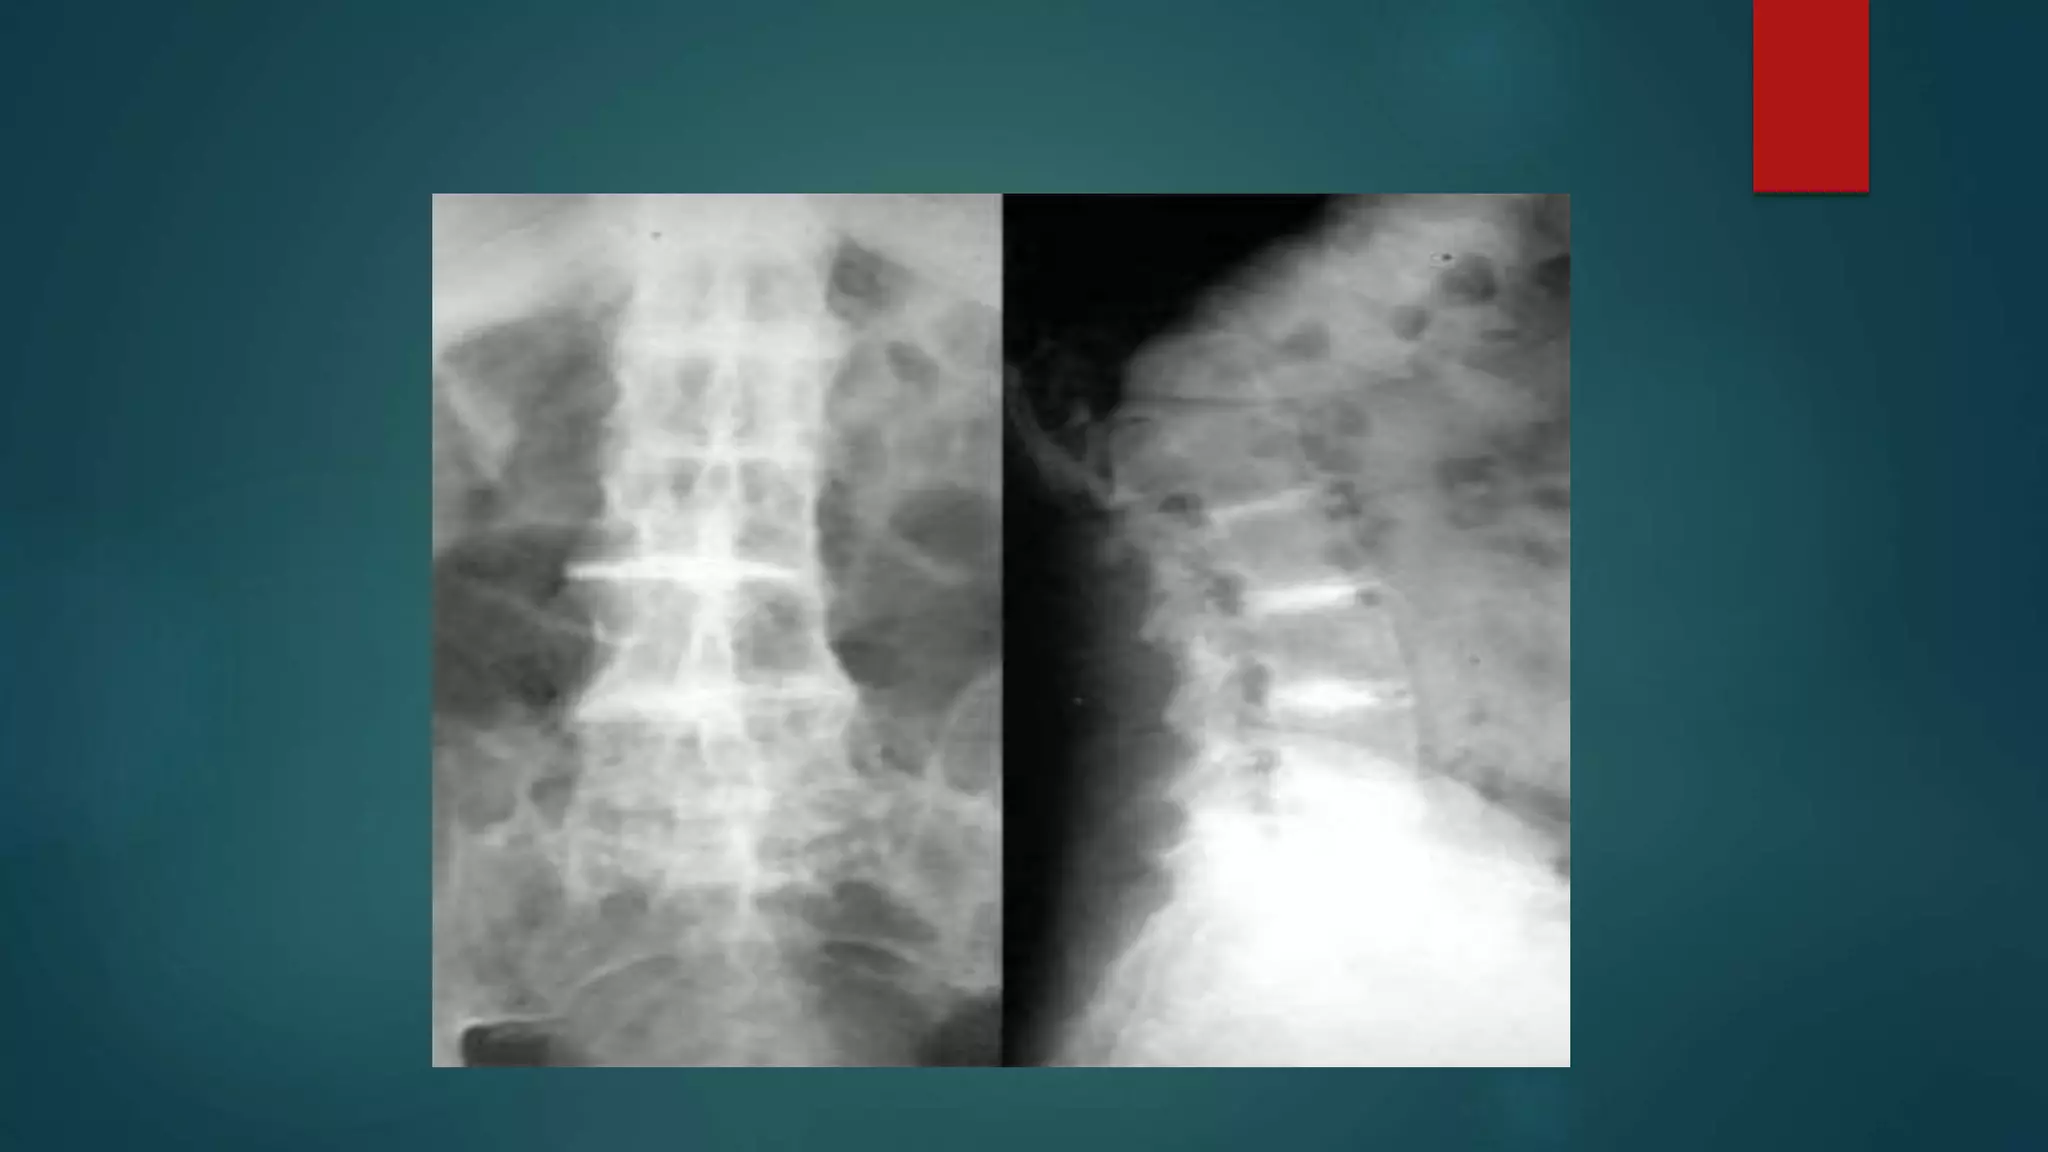

• #77 1.chalk stick fracture-Single sagittal image of the lumbar spine demonstrates a fracture extending from the anterior disc margin, through the inferior body of L1 and through the posterior elements. Note extensive syndesmophytic fusion of the discs spaces and posterior elements consistent with ankylosing spondylitis. 2.Typical features of ankylosing spondylitis with syndesmophytes, bamboo spine and bony fusion of posterior elements (dagger sign). 3.Throughout the spine, the vertebral bodies are fused by marginal syndesmophytes giving the appearance of Bamboo spine.